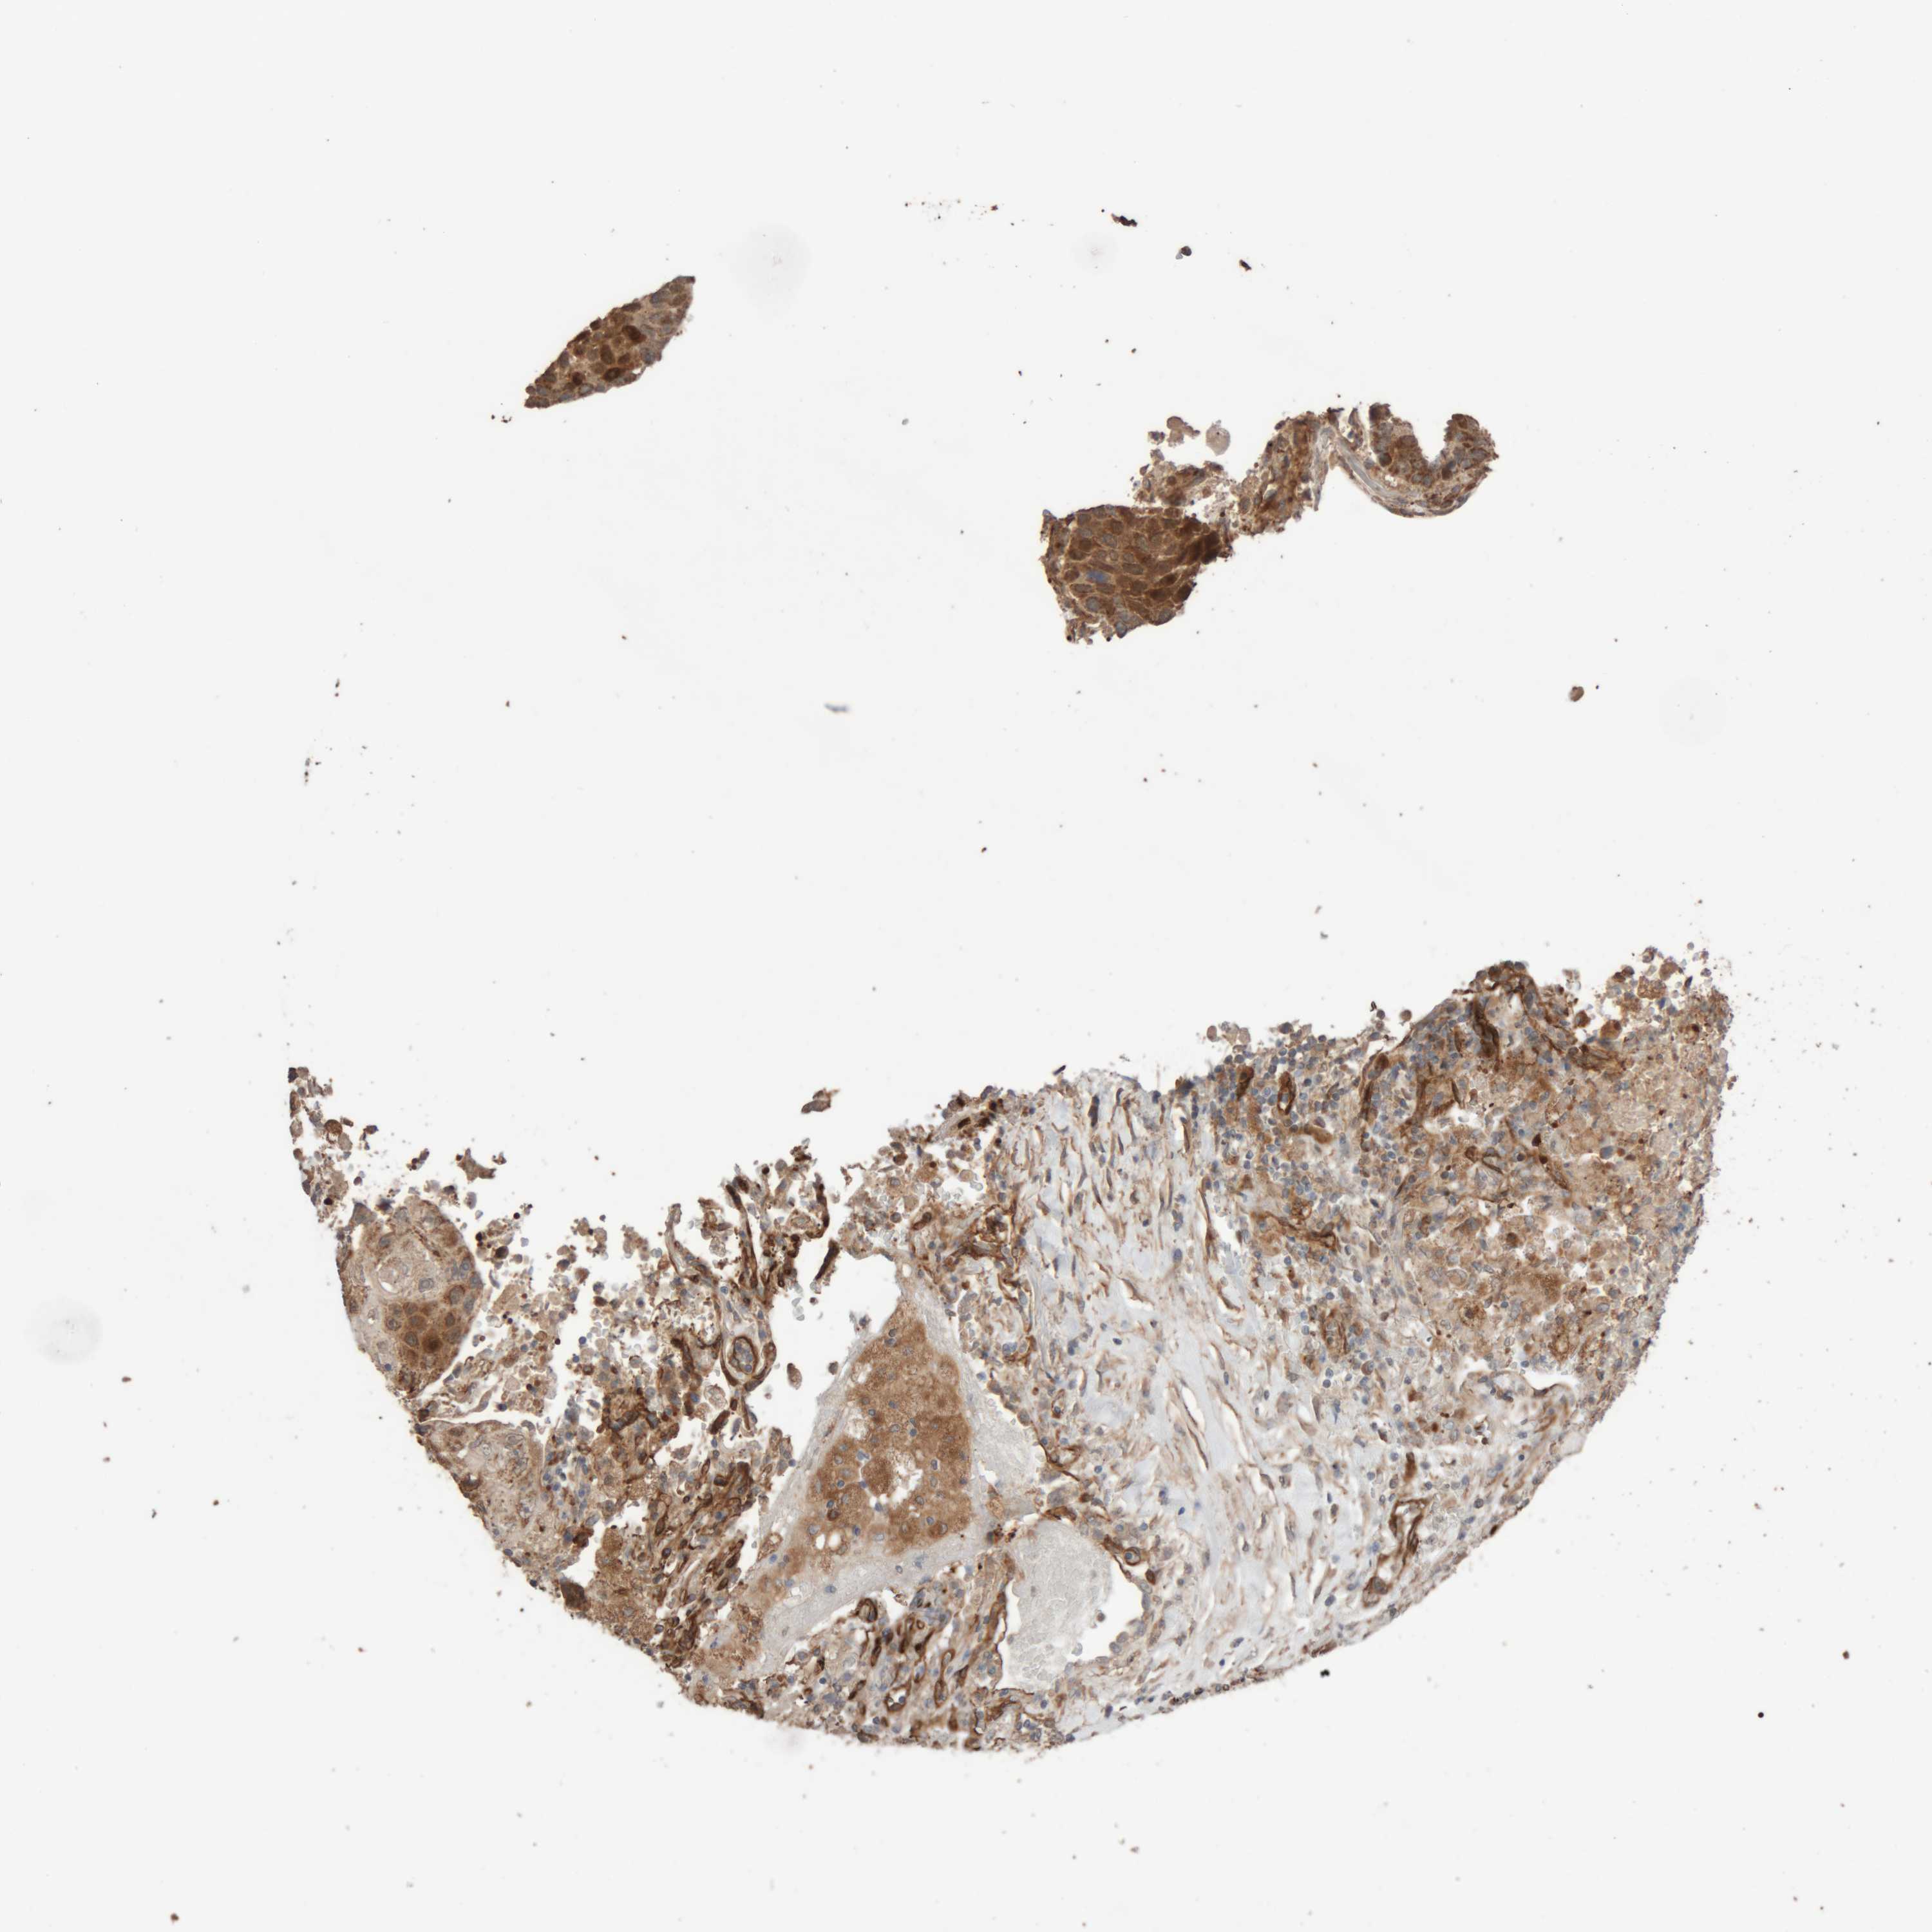

CANCER LUNG CANCER Show tissue menu

LUAD TCGA LUAD VALIDATION LUSC TCGA LUSC VALIDATION PROTEIN LUAD CPTAC PROTEIN LUSC CPTAC PROTEIN EXPRESSION